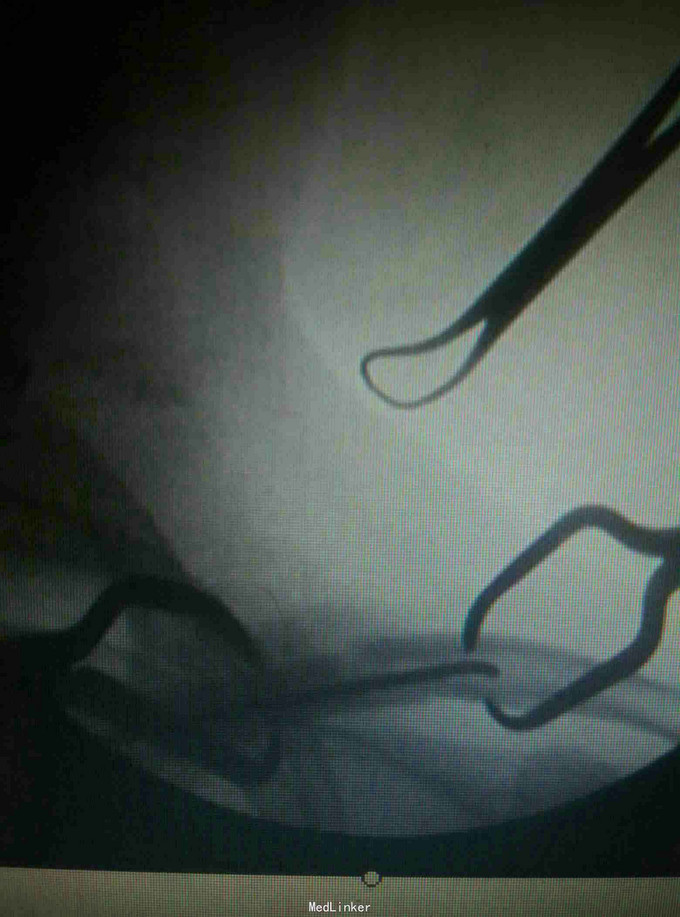

诊断:左锁骨骨折, 治疗:闭合复位TEN固定术

术后恢复良好,术后4个月拔除TEN 讨论:大部分锁骨骨折可以通过闭合复位钢针固定,但如果是骨质疏松病人,容易出现松动或退针等可能。而TEN更具有抗弯曲稳定,抗旋转稳定,横向稳定,轴向稳定,所以骨质比较疏松患者,我们采用TEN进行固定。